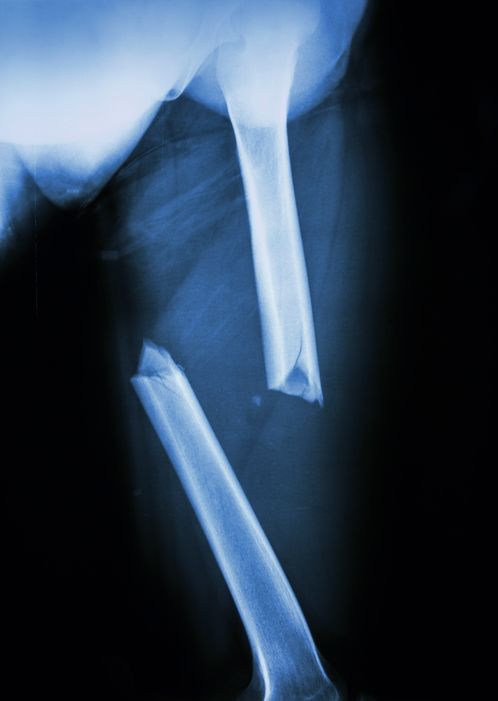

대퇴부 골절, 통증, 대퇴부 위치, 수술, 치료법에 대해서 알아보겠습니다. 대퇴부 골절은 허벅지뼈에 골절이 생긴 상태를 의미하며, 주로 대퇴골 몸통이나 대퇴 경부 부위에 발생합니다.

대퇴골은 신체에서 가장 크고 강한 뼈 중 하나로 골절이 발생하면 뼈 자체의 손상뿐 아니라 주변 근육과 인대, 혈관 조직에도 영향을 줄 수 있습니다.

사고나 강한 충격에 의한 골절 외에도 뼈의 밀도가 감소한 상태에서 외상으로도 골절이 발생할 수 있습니다. 대퇴부 골절은 움직임, 체중 부하, 관절 기능과도 밀접하게 연관되어 있어 손상 범위를 정확히 파악한 후 적절한 조치가 필요합니다.

대퇴골의 구조적 이상

대퇴골 자체에 골절, 미세 골절, 혹은 골종양과 같은 구조적 변화가 생긴 경우에도 통증이 나타날 수 있습니다. 외부 충격 없이도 골절이 발생하는 경우는 뼈의 밀도가 약해진 상태일 수 있으며, 통증은 대개 일정 부위에 국한되어 나타납니다.

대퇴골의 특정 부위를 누를 때 압통이 있으며, 체중을 실을 때 통증이 더욱 심해지는 경향을 보입니다. 구조적 이상은 진행 정도에 따라 통증의 양상이나 지속 시간에도 차이를 보입니다.

골절이 발생한 경우 수술적 치료가 필요한 경우가 많습니다. 수술은 뼈의 유합을 돕고 조기 움직임을 가능하게 하는 데 목적이 있으며, 골절의 형태나 환자의 뼈 상태에 따라 수술 방식이 결정됩니다. 수술 이후에는 회복을 위한 집중적인 재활이 함께 진행되어야 기능 회복이 가능합니다.

내고정술

금속 내고정술은 대퇴골 골절 부위를 직접 노출시켜 골절된 뼈를 정복한 뒤, 금속판이나 나사, 나비못 등을 이용해 고정하는 수술입니다. 주로 대퇴골의 골간부나 대퇴경부 골절에서 시행되며, 뼈 조각의 위치가 어긋난 경우에 적합합니다.

수술 중에는 뼈의 정확한 정렬을 맞추는 것이 중요하며, 고정력이 충분하면 조기 보행 훈련도 가능합니다. 수술 후 일정 기간이 지나면 금속 고정물이 제거되기도 하나, 평생 유지하는 경우도 많습니다.